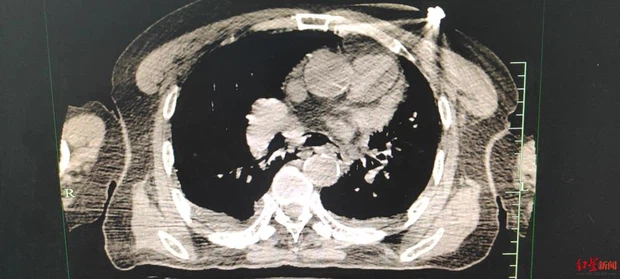

Hình ảnh chụp X-quang của ông Lý cho thấy thực quản bị vỡ, hở khoang ngực. |

Ông Lý (68 tuổi, Trung Quốc) thường xuyên bị nôn mửa và đau tức ngực sau khi ăn quá no, khi nhập viện thì phát hiện trên thực quản bị thủng một lỗ dài 5cm. Nếu không được mổ kịp thời, rất có thể tử vong do sốc độc do nhiễm trùng phổi.

Ngay sau đó, bệnh nhân được tiến hành phẫu thuật, sau khoản 3 tiếng để sửa chữa vỡ thực quản, dính màng phổi và dẫn lưu lồng ngực kín. Khi khám thực quản bị vỡ, bác sĩ phát hiện đoạn vỡ dài 5cm. May mắn thay, ca mổ của ông Lý đã được sửa chữa thành công. Sau 2 ngày điều trị tại phòng chăm sóc đặc biệt, ông Lý đã có thể trở lại khoa ngoại tổng hợp và được xuất viện sau hơn 20 ngày.